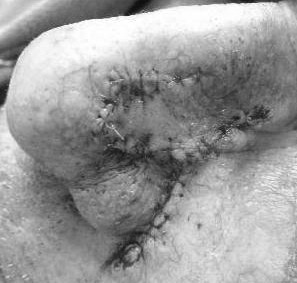

Figure showing the sutured wound